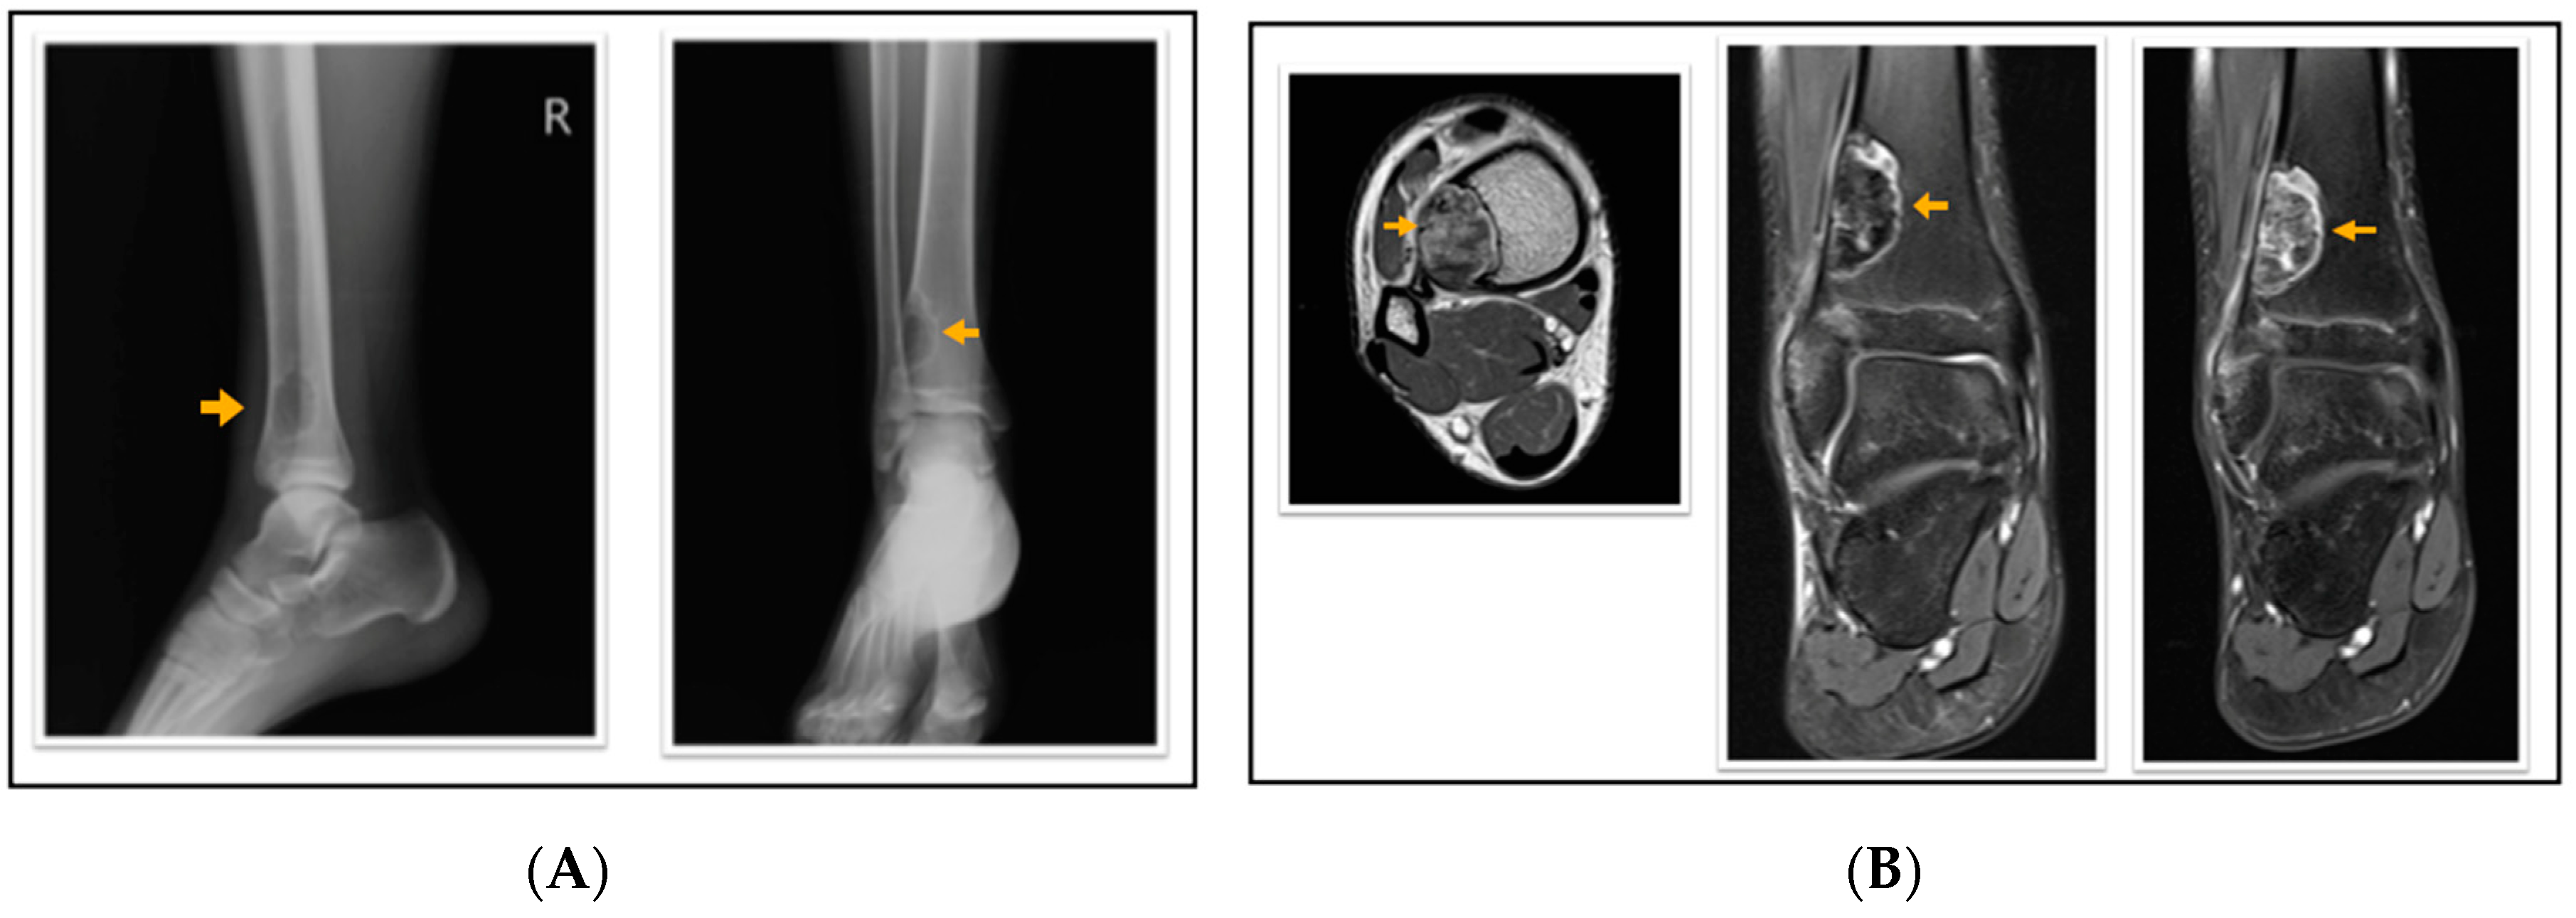

2.2. Radiological Evaluation of FCD/NOF